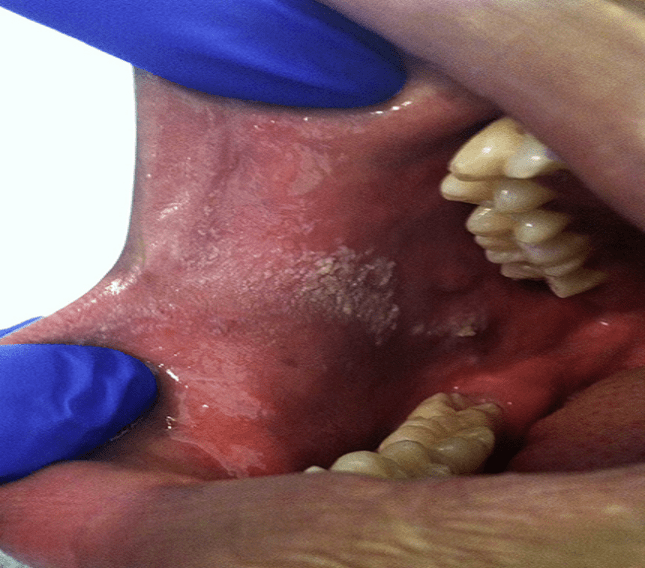

口腔增生

口腔黏膜长了斑,小心癌变!99%的风湿科医生都分辨不了

口腔上腭肿物

口腔白斑癌变

口腔上颚癌早期症状

口腔专业讨论版 -丁香园论坛